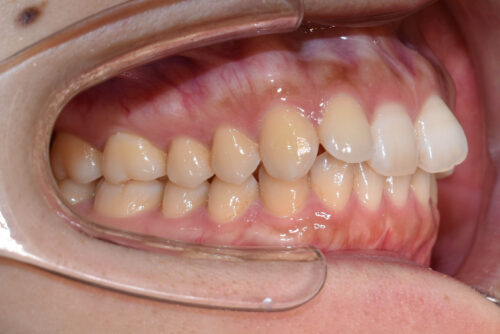

右側が アングル2級とよばれる

出っ歯傾向の状態で

上の正中が

半歯分 ずれている状態でした。